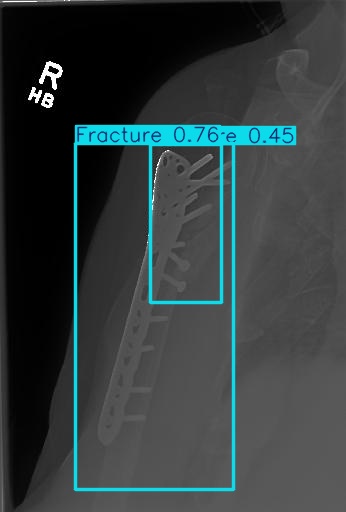

Bone 이미지 데이터 350장 중 Fracture 이미지 50장, Implant 이미지 50장, Bone 이미지 50장을 선별했다.

train과 val은 라벨링을 해야한다. 어제 라벨링을 했었지만, Fracture는 좀 넓게 잡고, Implant는 최대한 여러개로 쪼개는 느낌으로 라벨링을 다시했다.

20251204_03 predict

아 또 계정 바꾸면서 class 반대로 되어있는 파일로 넣었다

| iou | 0.5 | 줄여보기 |

아니 아까보다 더 안 좋아졌다.